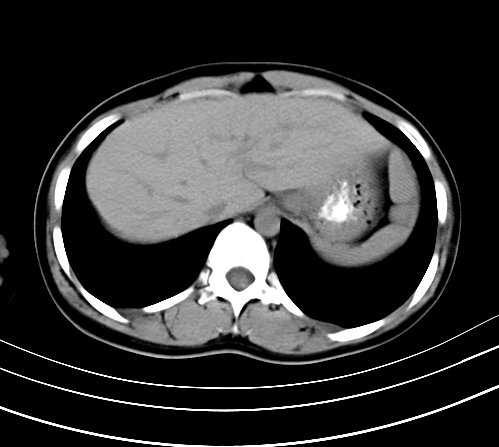

静脉期